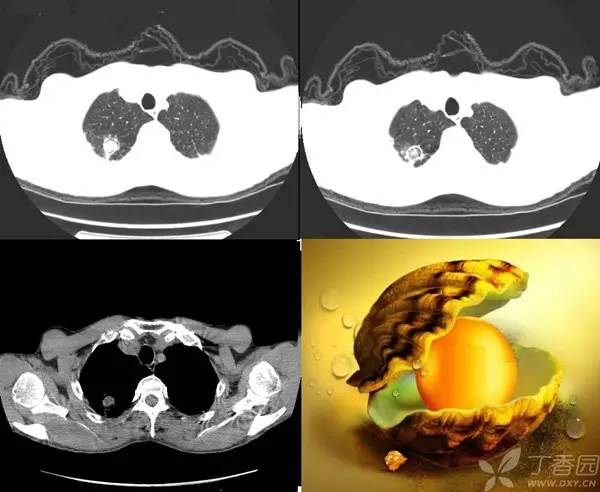

该征象通常被认为是曲菌移植到已有的空洞内或在血管侵袭性曲菌病中梗死的肺收缩的结果。但该征象也见于其他情况,包括结核病、Wegener 肉芽肿、空洞内出血和肺癌。

真菌感染的早期 X 线表现可能正常,之后出现但发或多发边界不清的周围性斑片状影,最后呈大片状或结节、或肿块抑或粟粒状,大约半个月后出现空气半月征(发生率约 50%)。